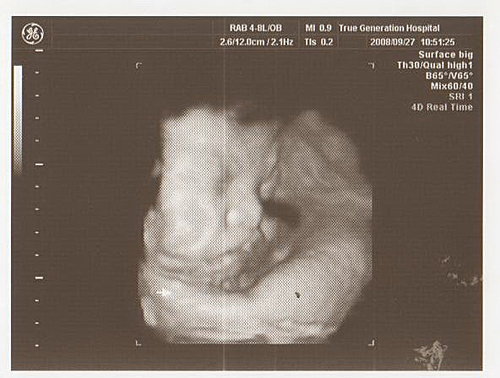

超音波檢查

先量頭圍、腹圍和大腿骨的長度

寶寶的體重大約2800公克

嚇了我一大跳

居然一星期就增加300公克

接著看心臟

很有規律的跳動

腎臟的發育也正常